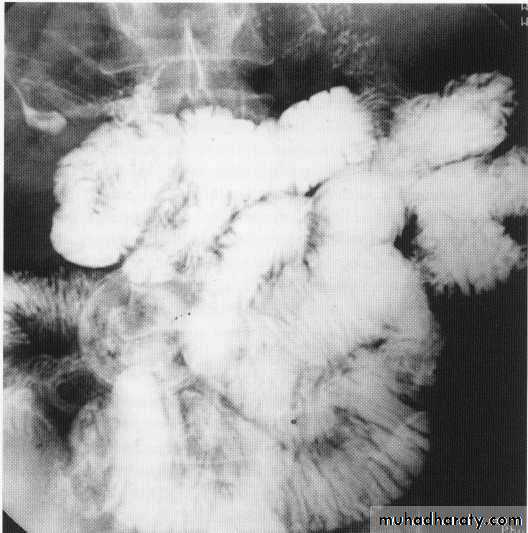

Small bowel lymphoma

Small bowel tumor